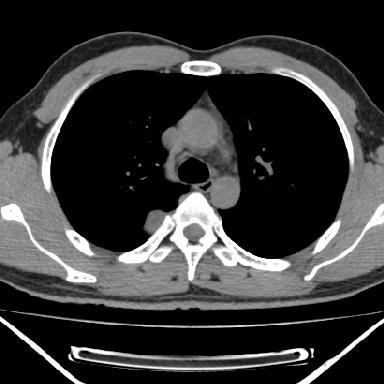

m 30 右胸痛10年

右上后纵隔脊柱旁类圆形肿块,边界光整,与胸腔呈钝角,首先考虑来源于肺外,神经源性肿瘤(神经鞘瘤可能大,神经鞘瘤)

病灶与椎间孔间存在脂间隙,病灶较大,椎间无明显异常改变,与胸膜移行处可见尾状影,考虑胸膜肿瘤,以良性间皮瘤可能性大

病灶最大径线处于肋间隙,不排除起源于肋神经源性肿瘤

右上后纵隔旁软组织肿块影,与肺界面光滑,与胸壁呈钝角相交,提示肺外病变。位于肋骨下缘,边缘清楚,呈三角样指向与右侧椎间孔,但并示进入椎间孔;与对侧神经根对比,属同一走行方向。

考虑后纵膈良性肿瘤,神经源性肿瘤可能大。

右上后纵隔脊柱旁类圆形肿块,边界光整,与胸腔呈钝角,首先考虑来源于纵膈,神经源性肿瘤可能大。

右上后纵隔脊柱旁见长椭圆形肿块,边界光整,与胸壁呈钝角。周围骨质未见异常。

考虑、1、后纵隔神经源性肿瘤;

2、不除外单发胸膜间皮瘤。